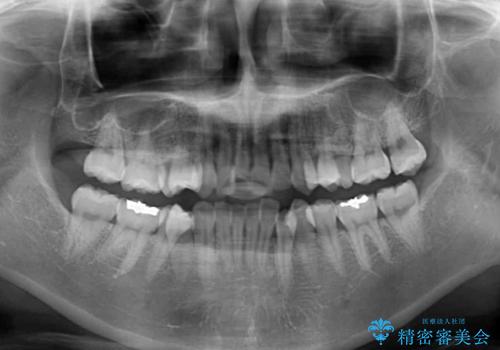

- 上下の歯の前後関係が乱れ、歯に負担がかかるとのことで来院された患者様です。

下顎が右左側に変位しているため、左側奥歯の咬み合わせが上下反対の関係となっていました。

また、上下ともに歯列が狭窄しており、奥歯以外にも反対咬合が認められました。